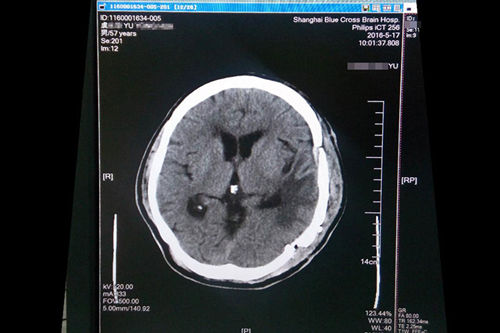

2016年4月,浙江宁波人,57岁的虞文军(化名)因巨大脑肿瘤(8*6cm) 前来上海蓝十字脑科医院就诊。经包括沈建康教授在内的专家会诊后,考虑到患者脑肿瘤巨大、肿瘤周边血供丰富,手术指征明确,常规手术切除恐出血过多,增加手术风险,决定术前先为虞文军行“超选择性全脑血管造影术+脑膜瘤供血动脉栓塞术”,对肿瘤供血动脉进行栓塞,减少出血量,再全麻下行“左侧颞底部巨大脑膜瘤切除术”。沈教授已经有十年未见过患者有如此大的肿瘤,患者术后随即恢复清醒,自我感觉头脑较前更清醒,语音、语速恢复较好,不到半个月便已能正常行走,顺利出院。

沈建康教授为虞文军成功施行巨大肿瘤切除术

术前磁共振影像显示巨大脑肿瘤

术后一个月复查CT影像显示恢复良好